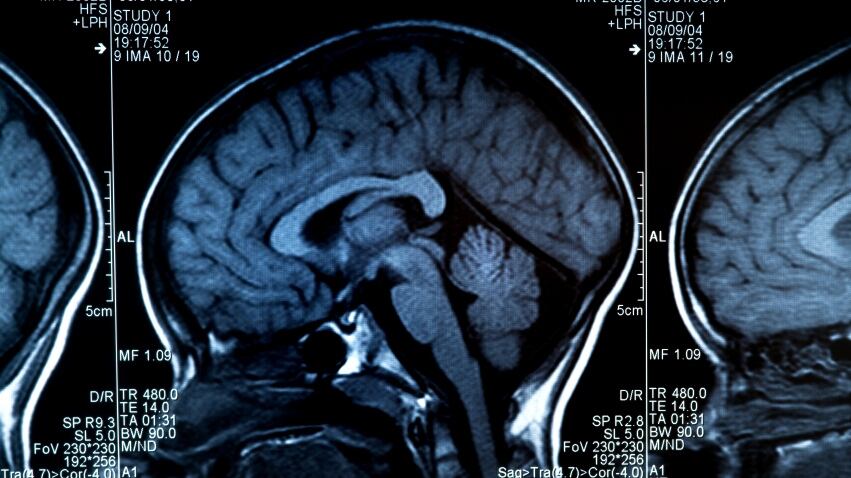

More Ontario children, youth being treated for concussions: study